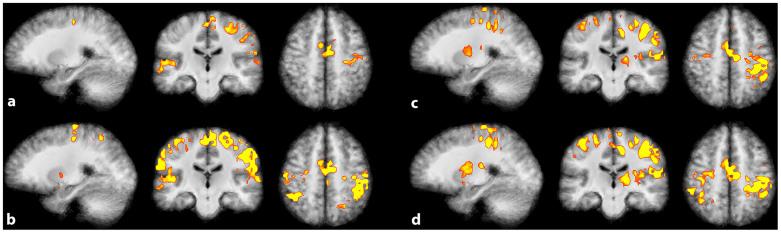

Real-time functional Magnetic Resonance Imaging (rtfMRI) is used mainly for neurofeedback or for brain-computer interfaces (BCI). But multi-site rtfMRI could in fact help in the application of new interactive paradigms such as the monitoring of mutual information flow or the controlling of objects in shared virtual environments. For that reason, a previously developed framework that provided an integrated control and data analysis of rtfMRI experiments was extended to enable multi-site rtfMRI. Important new components included a data exchange platform for analyzing the data of both MR scanners independently and/or jointly. Information related to brain activation can be displayed separately or in a shared view. However, a signal calibration procedure had to be developed and integrated in order to permit the connecting of sites that had different hardware and to account for different inter-individual brain activation levels. The framework was successfully validated in a proof-of-principle study with twelve volunteers. Thus the overall concept, the calibration of grossly differing signals, and BCI functionality on each site proved to work as required. To model interactions between brains in real-time, more complex rules utilizing mutual activation patterns could easily be implemented to allow for new kinds of social fMRI experiments.

实时功能磁共振成像(rtfMRI)主要用于神经反馈或脑机接口(BCI)。但事实上,多站点rtfMRI有助于新交互范式的应用,如监测互信息流或在共享虚拟环境中控制对象。因此,一个先前开发的用于rtfMRI实验综合控制和数据分析的框架被扩展以支持多站点rtfMRI。重要的新组件包括一个数据交换平台,用于独立和/或联合分析两台磁共振扫描仪的数据。与大脑激活相关的信息可以单独显示或在共享视图中显示。然而,必须开发并集成一个信号校准程序,以允许连接具有不同硬件的站点,并考虑个体间不同的大脑激活水平。该框架在一项有12名志愿者参与的原理验证研究中得到成功验证。因此,整体概念、对差异极大的信号进行校准以及每个站点的BCI功能均按要求运行。为了实时模拟大脑之间的交互,可以轻松实施利用相互激活模式的更复杂规则,以开展新型社会功能磁共振成像实验。